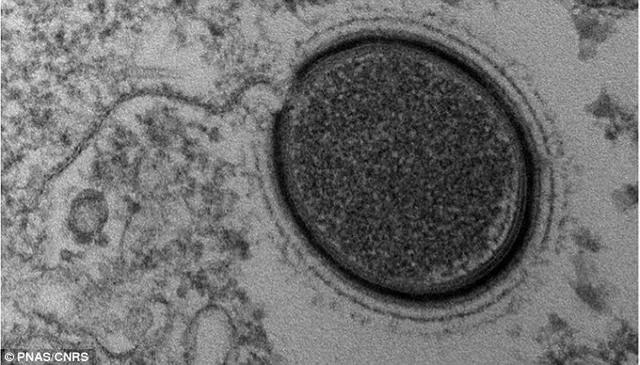

最新病毒大小,观点论述与深度解析

摘要:关于最新病毒大小的观点论述,目前科学家们正在深入研究。病毒的大小因种类而异,其结构复杂且微小。随着科技的不断进步,我们能够更准确地测量病毒的大小。最新研究表明,某些病毒的大小可能比我们之前认为的要小或更大,这对...